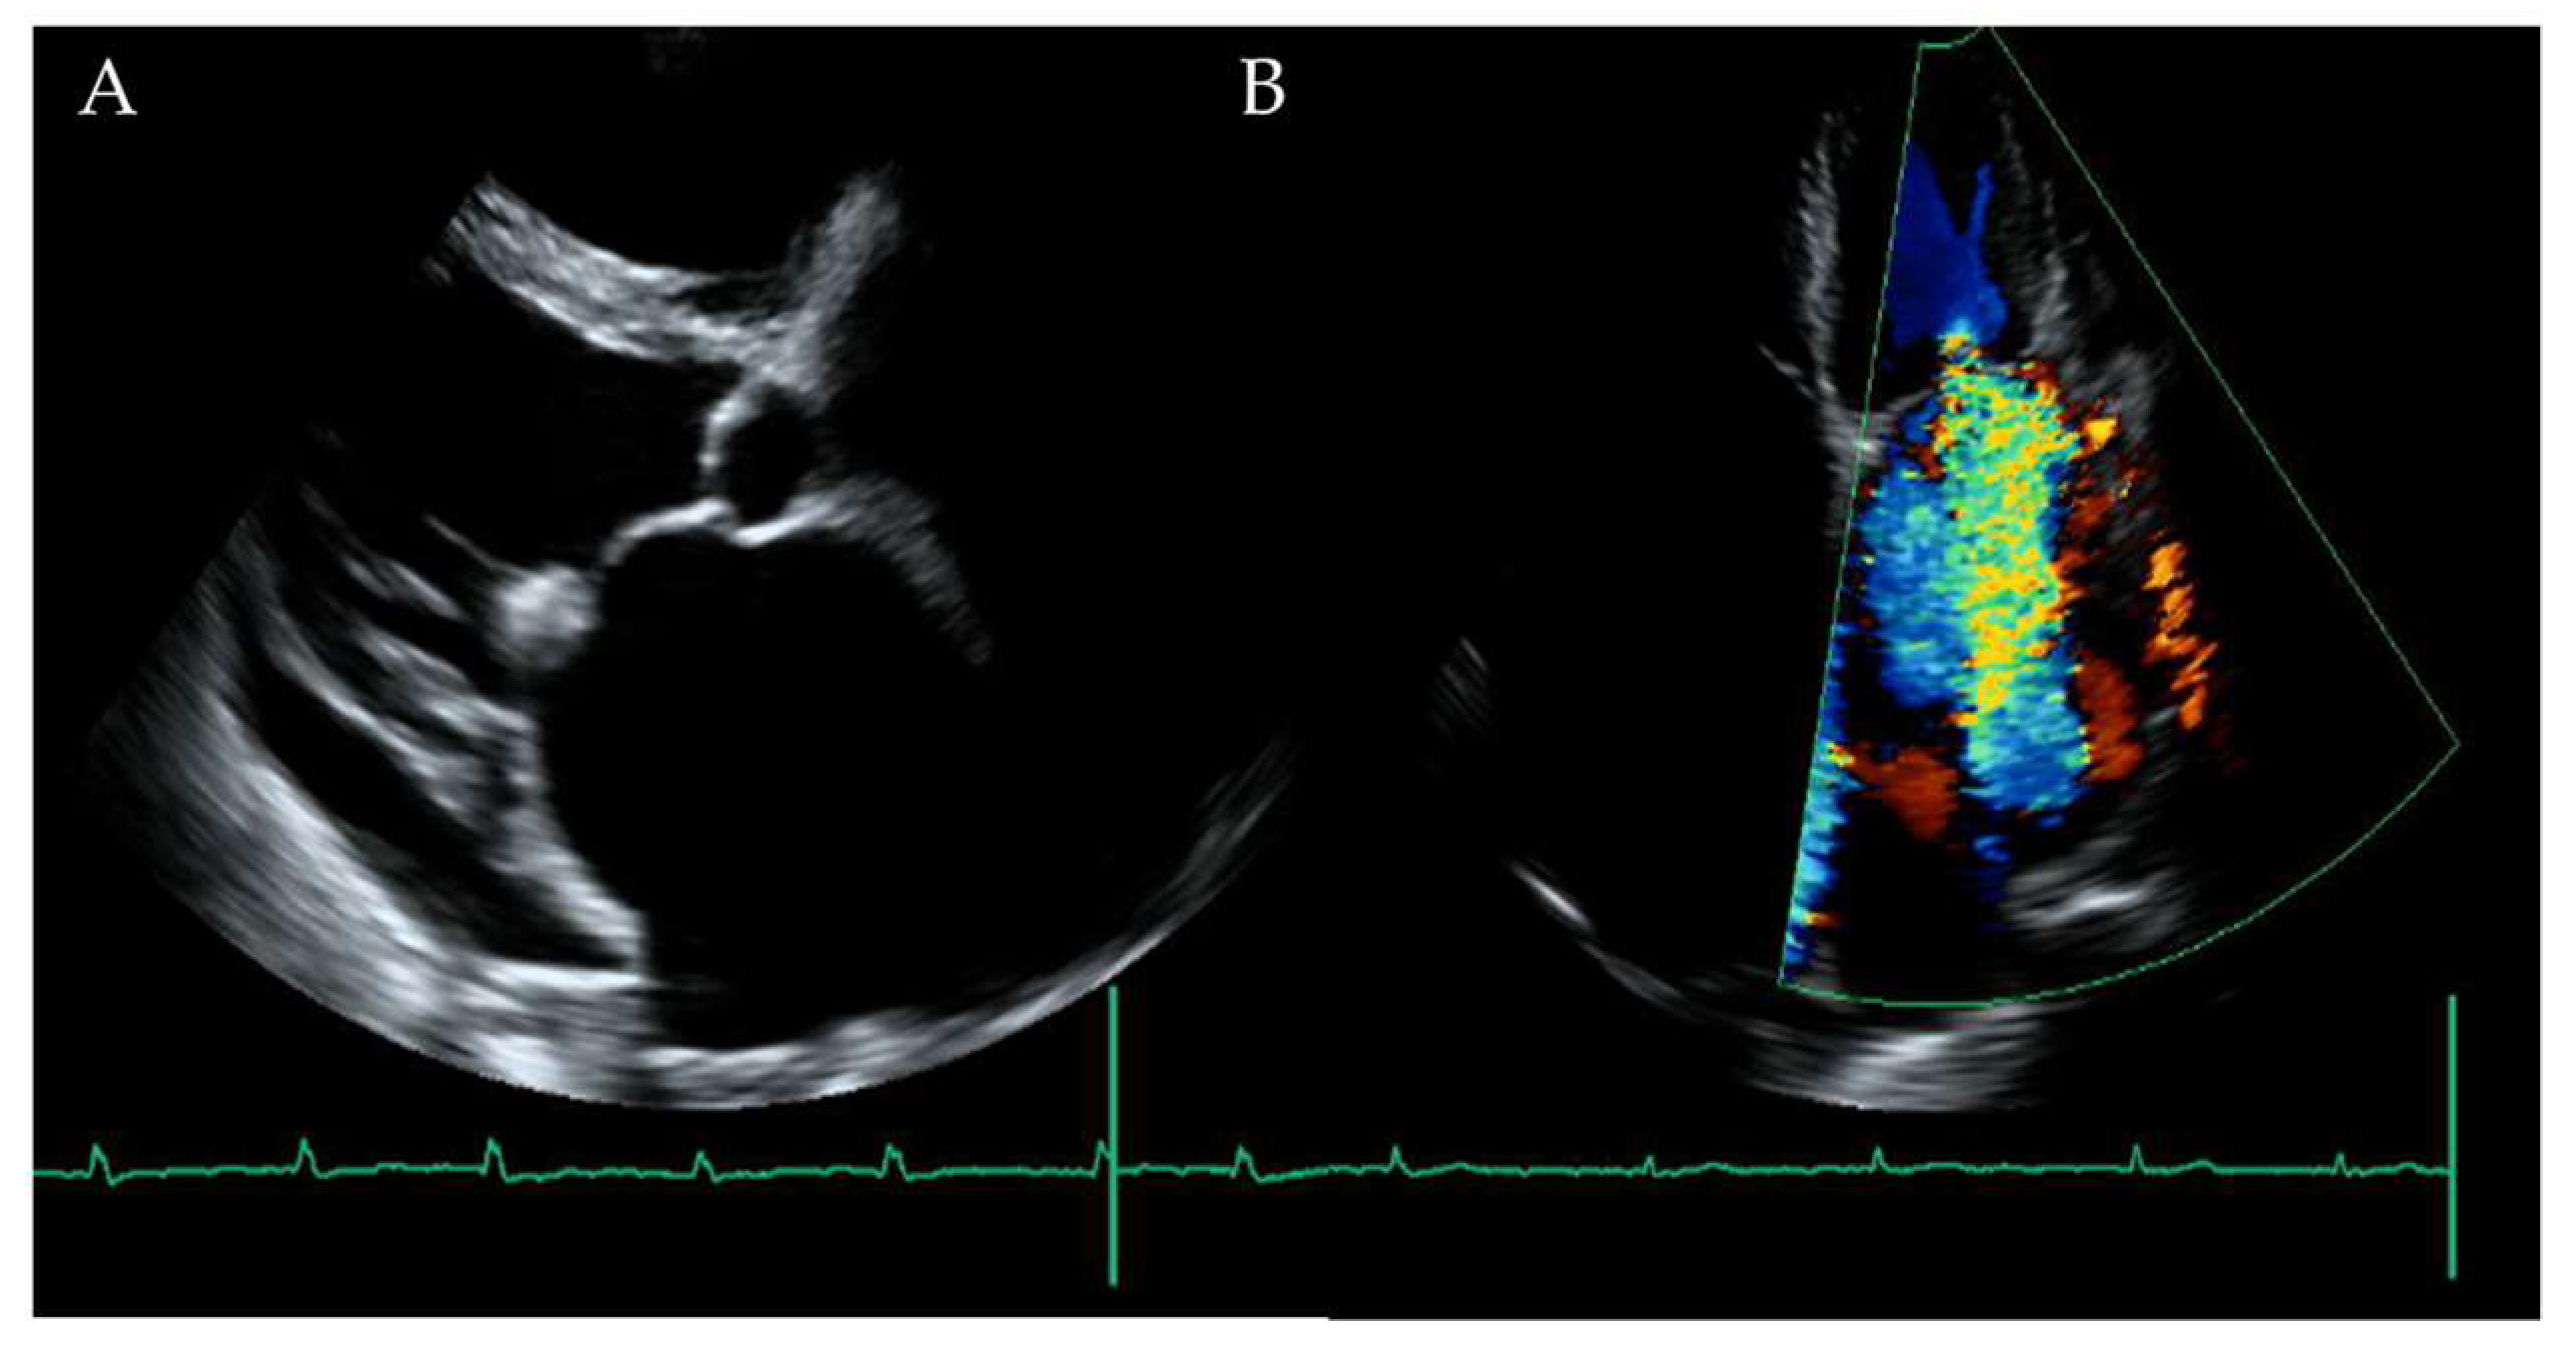

2. Case Presentation